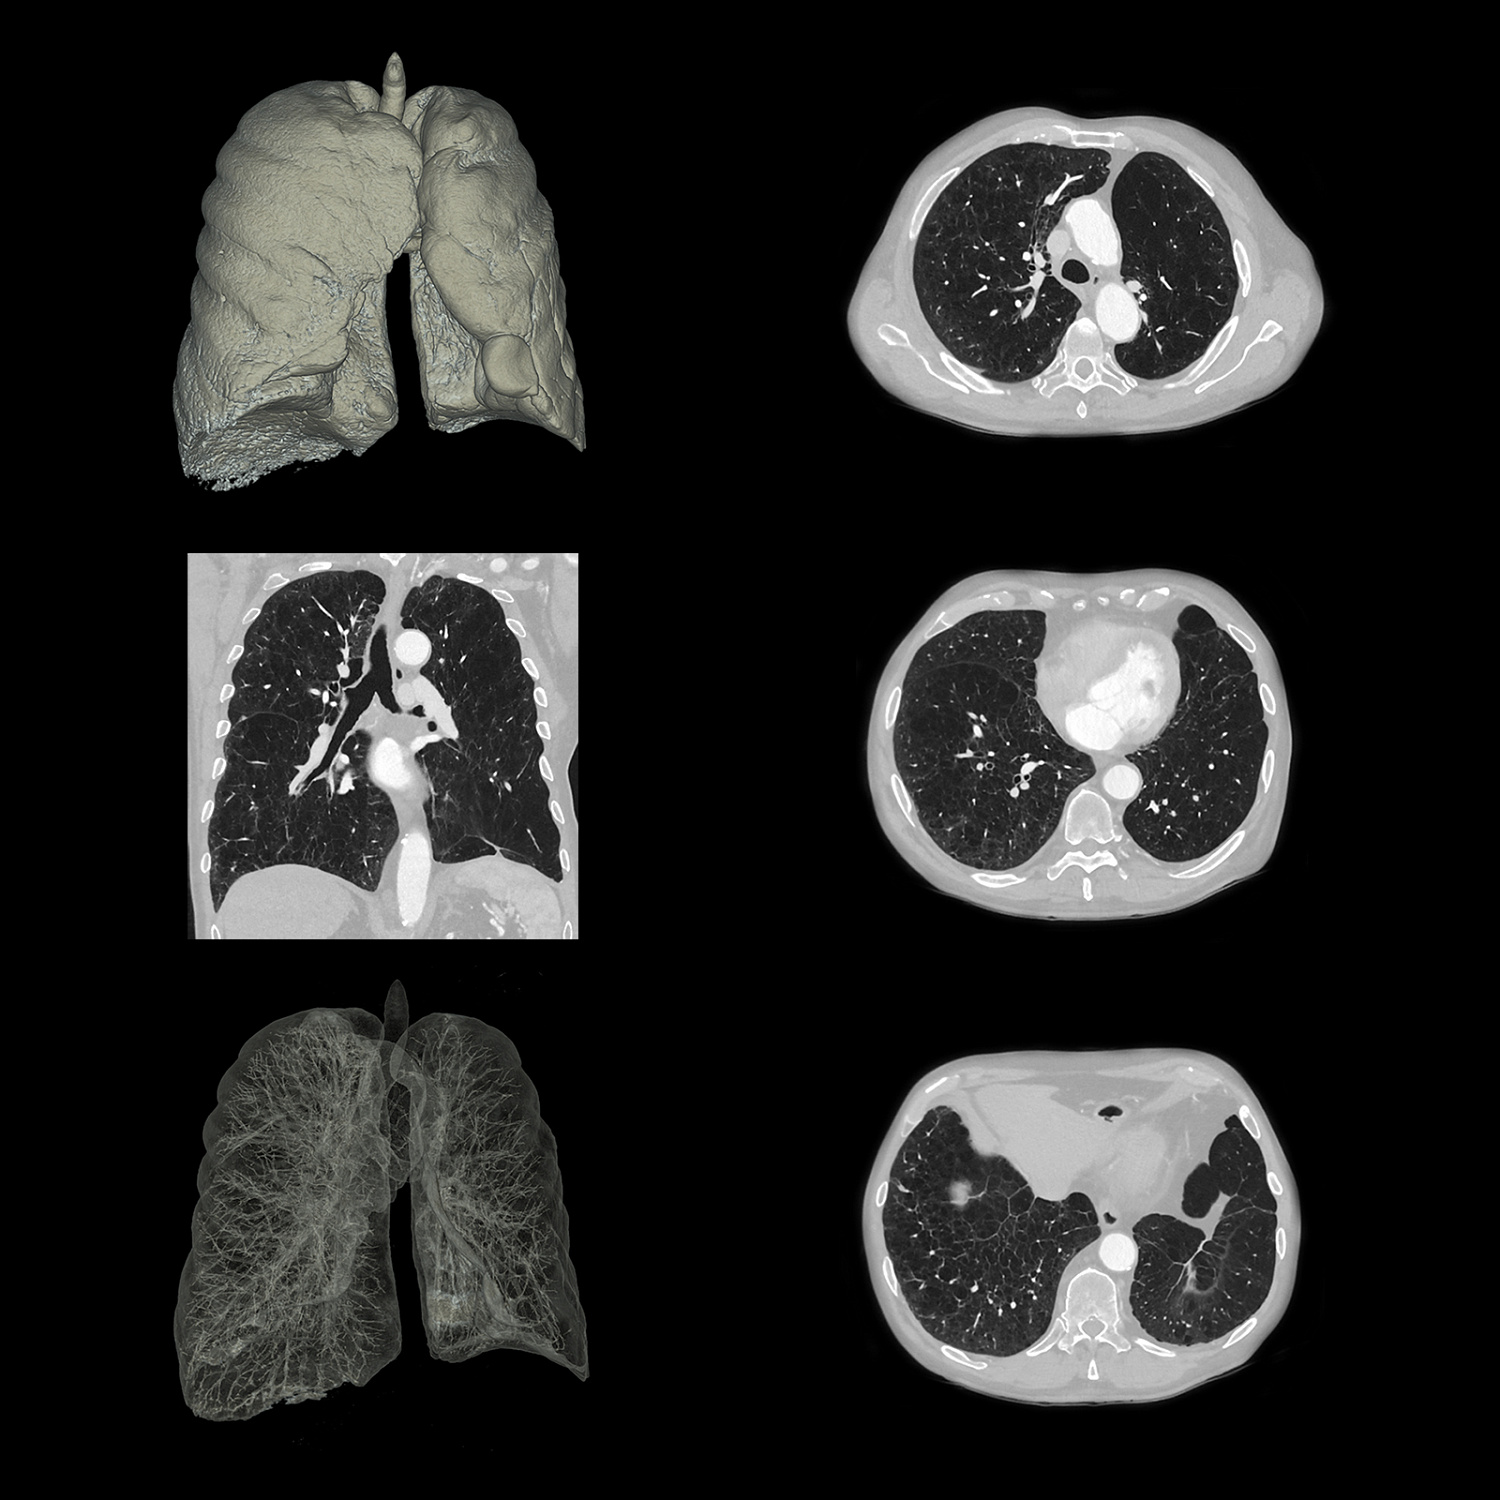

Фильтр SilverBeam

SilverBeam, энергетический фильтр, формирующий луч, использует свойства серебра по ослаблению фотонов для выборочного удаления фотонов низкой энергии из полихроматического рентгеновского луча, оставляя энергетический спектр, оптимизированный для скрининга рака легких.

КТ-скрининг рака легких при уровнях доз, приближающихся к обычной рентгенографии

Разработанный для работы в сочетании с AiCE, SilverBeam предоставляет улучшенные, высококачественные, малошумящие КТ-снимки скрининга рака легких при дозе облучения порядка типичного рентгенологического исследования грудной клетки.

SilverBeam с AiCE можно использовать для надежной организации службы скрининга рака легких в вашей больнице.

Расширенный интеллектуальный модуль Clear-IQ Engine (AiCE)

КТ-реконструкция, в которой используются инновации глубокого обучения, чтобы соответствовать пространственному разрешению и малошумным свойствам усовершенствованных итеративных реконструкций на основе моделей для получения высококачественных изображений без ущерба для скорости или дозы.

- Малый шум

- Естественная текстура изображения

- Четкое высококонтрастное разрешение

- Четкая низкоконтрастная детектируемость